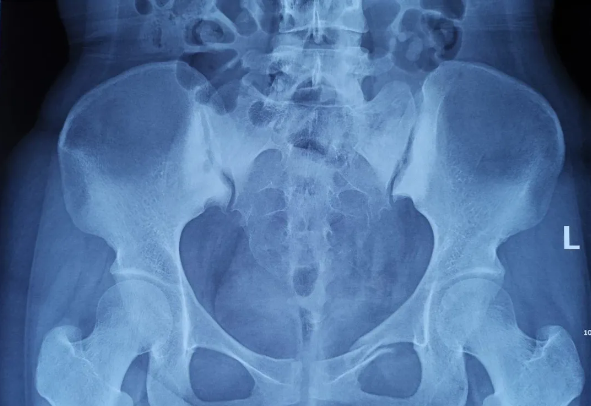

2025-02-28智匯天璣|高齡不是禁區!北京積水潭醫院智能骨科機器人助力90歲骨盆骨折患者重獲行走

由北京積水潭醫院院長蔣協遠、智能骨科研究型病房主任王軍強帶領的智能骨科團隊,運用骨科機器人輔助經皮骨盆通道螺釘置入技術,成功救治了一名90歲高齡的骨盆骨折患者。 -

2021-01-06天璣骨科手術機器人落戶南昌市第一醫院,助力骨盆骨折閉合復位內固定術順利完成

近日,天璣?骨科手術機器人落戶南昌市第一醫院,助力骨盆骨折閉合復位內固定術順利完成。作為江西省首先采用5G引導下的骨科機器人手術,天璣?骨科手術機器人用它的“透視眼”,以三維影像掃描進行深層三維空間精準定位,為患者“量身定做”了最理想、最安全的教科書般通道,完成了復雜骨盆骨折微創治療一次性完美置釘及腰椎骨折微創經皮置釘的首秀,成為江西省骨科發展的標志性事件,同時也是江西省骨科步入新型數字智慧骨科時代的重要里程碑事件。 -